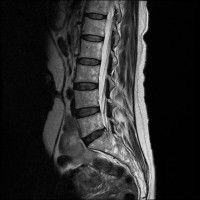

목,허리 디스크 엠알 판독.....

경추 요추 디스크 둘다 있는 상태고 경추몇번에서 몇번사이 요추몇번에서 몇번사이인지 알려주세요

허리

• 4번 째 사진